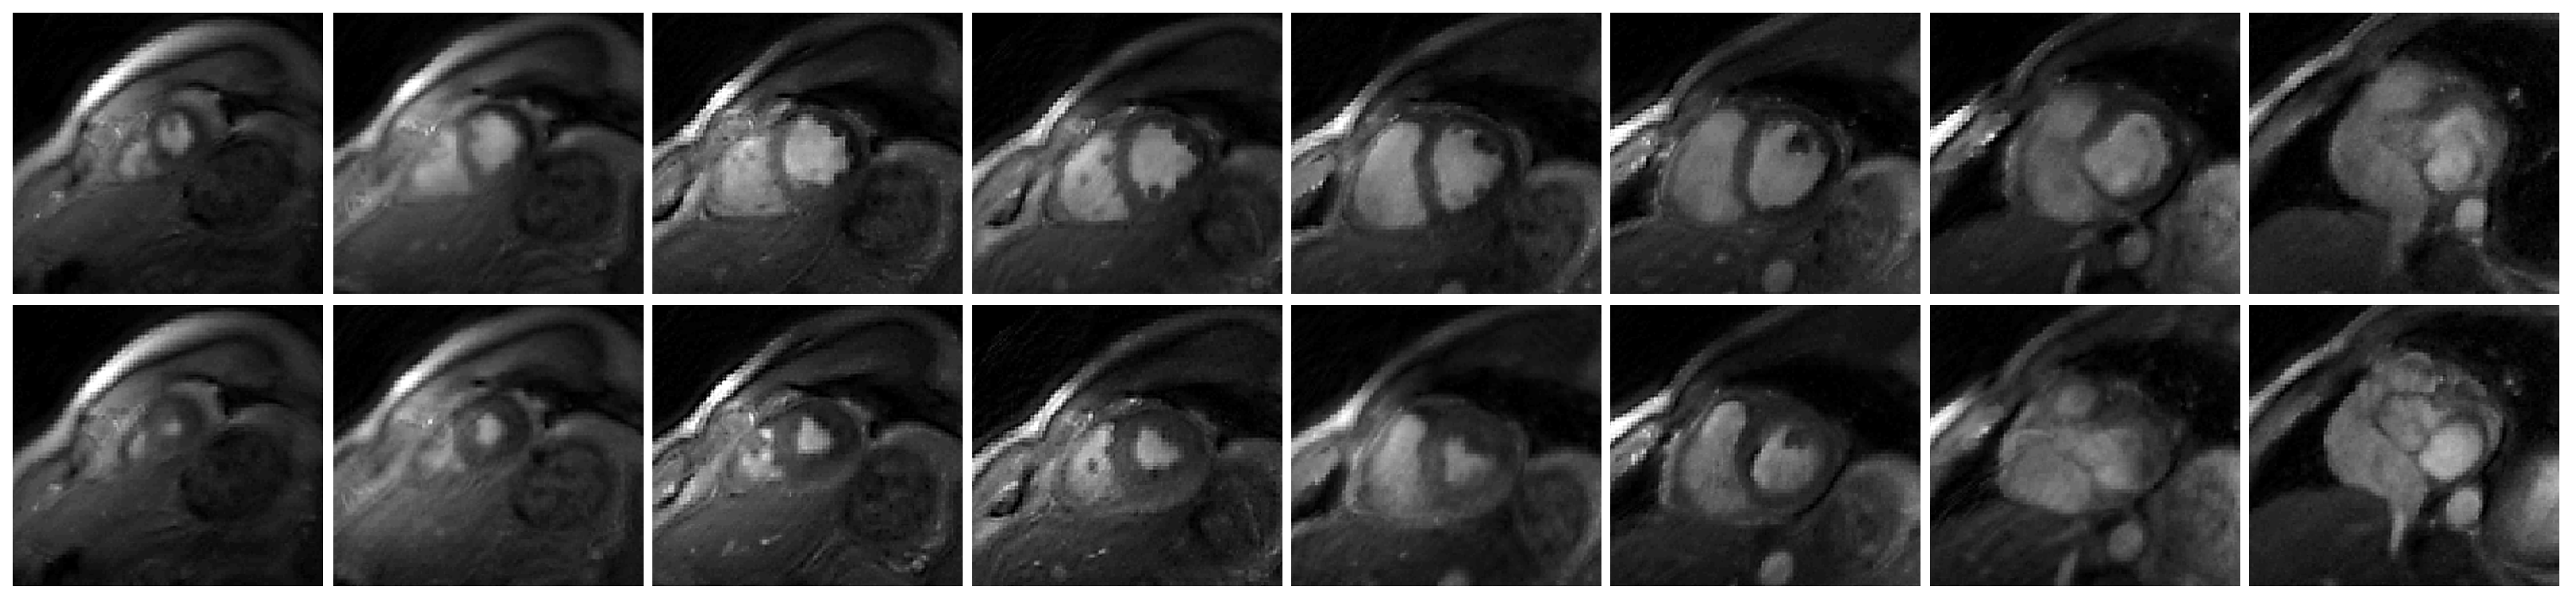

The output of each image has two channels, which correspond to the real and imaginary parts of the MR image. For the convolutional layers which have activation functions, we use Leaky ReLU with slope 0.2. Thirty-seven slices from five subjects were reconstructed in this work. Among the five subjects, we collected the basal slices for two subjects. The deep kernel method is also able to reconstruct the basal slices. The reconstructions of eight slices from Subject #2 were shown in Figure 2. We have also shown the comparison between the bSSFP Cartesian real-time images with acceleration factor 5 and the GRE spiral real-time images reconstructed using the deep kernel method in Figure 3.

Figure 2.

Showcase of the reconstruction of free-breathing and ungated cardiac MRI using the proposed deep kernel method. The eight slices are from Subject #2. The first row shows the end-diastolic phase, and the second row is the end-systolic phase.